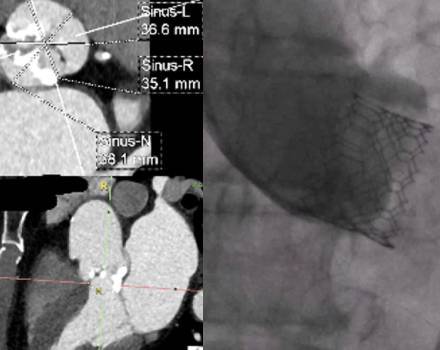

Valvular Heart Disease

The human heart consists of four separate chambers. The connection between these chambers, as well as with the body’s major blood vessels, is regulated by the cardiac valves. Proper heart function requires the coordinated operation of all its structures.

Valvular heart disease refers to the dysfunction of one or more of the heart valves.

Βαλβιδοπάθειες

Η ανθρώπινη καρδιά αποτελείται από 4 διαφορετικά “διαμερίσματα”. Η σύνδεση μεταξύ των διαμερισμάτων, αλλά και με τα μεγάλα αγγεία του σώματος, ορίζεται από τις καρδιακές βαλβίδες. Η καλή λειτουργία της καρδιάς απαιτεί την αρμονική λειτουργία όλων των δομών της.

Η δυσλειτουργία μιας (ή περισσότερων) των καρδιακών βαλβίδων, συνιστά τις βαλβιδοπάθειες.